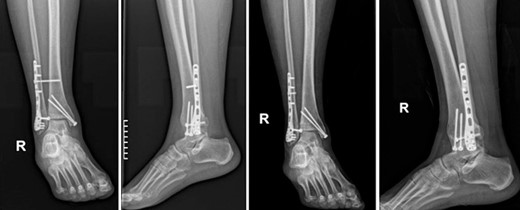

During the 6-month regular follow-up period, the patient reported discomfort and pain while walking and had an American Orthopaedic Foot and Ankle Society (AOFAS) score of 76. At this time, blood tests were negative for infection accounting: white blood cells (WBC) = 7,6 × 103/μl (normal values = 4.6–10.2 × 103/μl), C-reactive protein (CRP) < 0.31 mg/dl (normal values <0,31 mg/dl), and erythrocyte sedimentation rate (ESR) = 14 mm/h (normal values = 0–20 mm/h). A decision was made to remove the hardware, however, due to the patient’s COVID infection the intervention was postponed. Eight months postoperatively, hardware was removed due to surgical site pain, exacerbated by the patient’s inability to tolerate the discomfort at the surgery site.

The patient received the same antibiotics for chemoprophylaxis. During the procedure, surgical debridement was performed. Six specimens of soft tissue cultures were obtained during the hardware removal, and a sonication of the plate and the screws was conducted by the Department of Microbiology of our hospital.